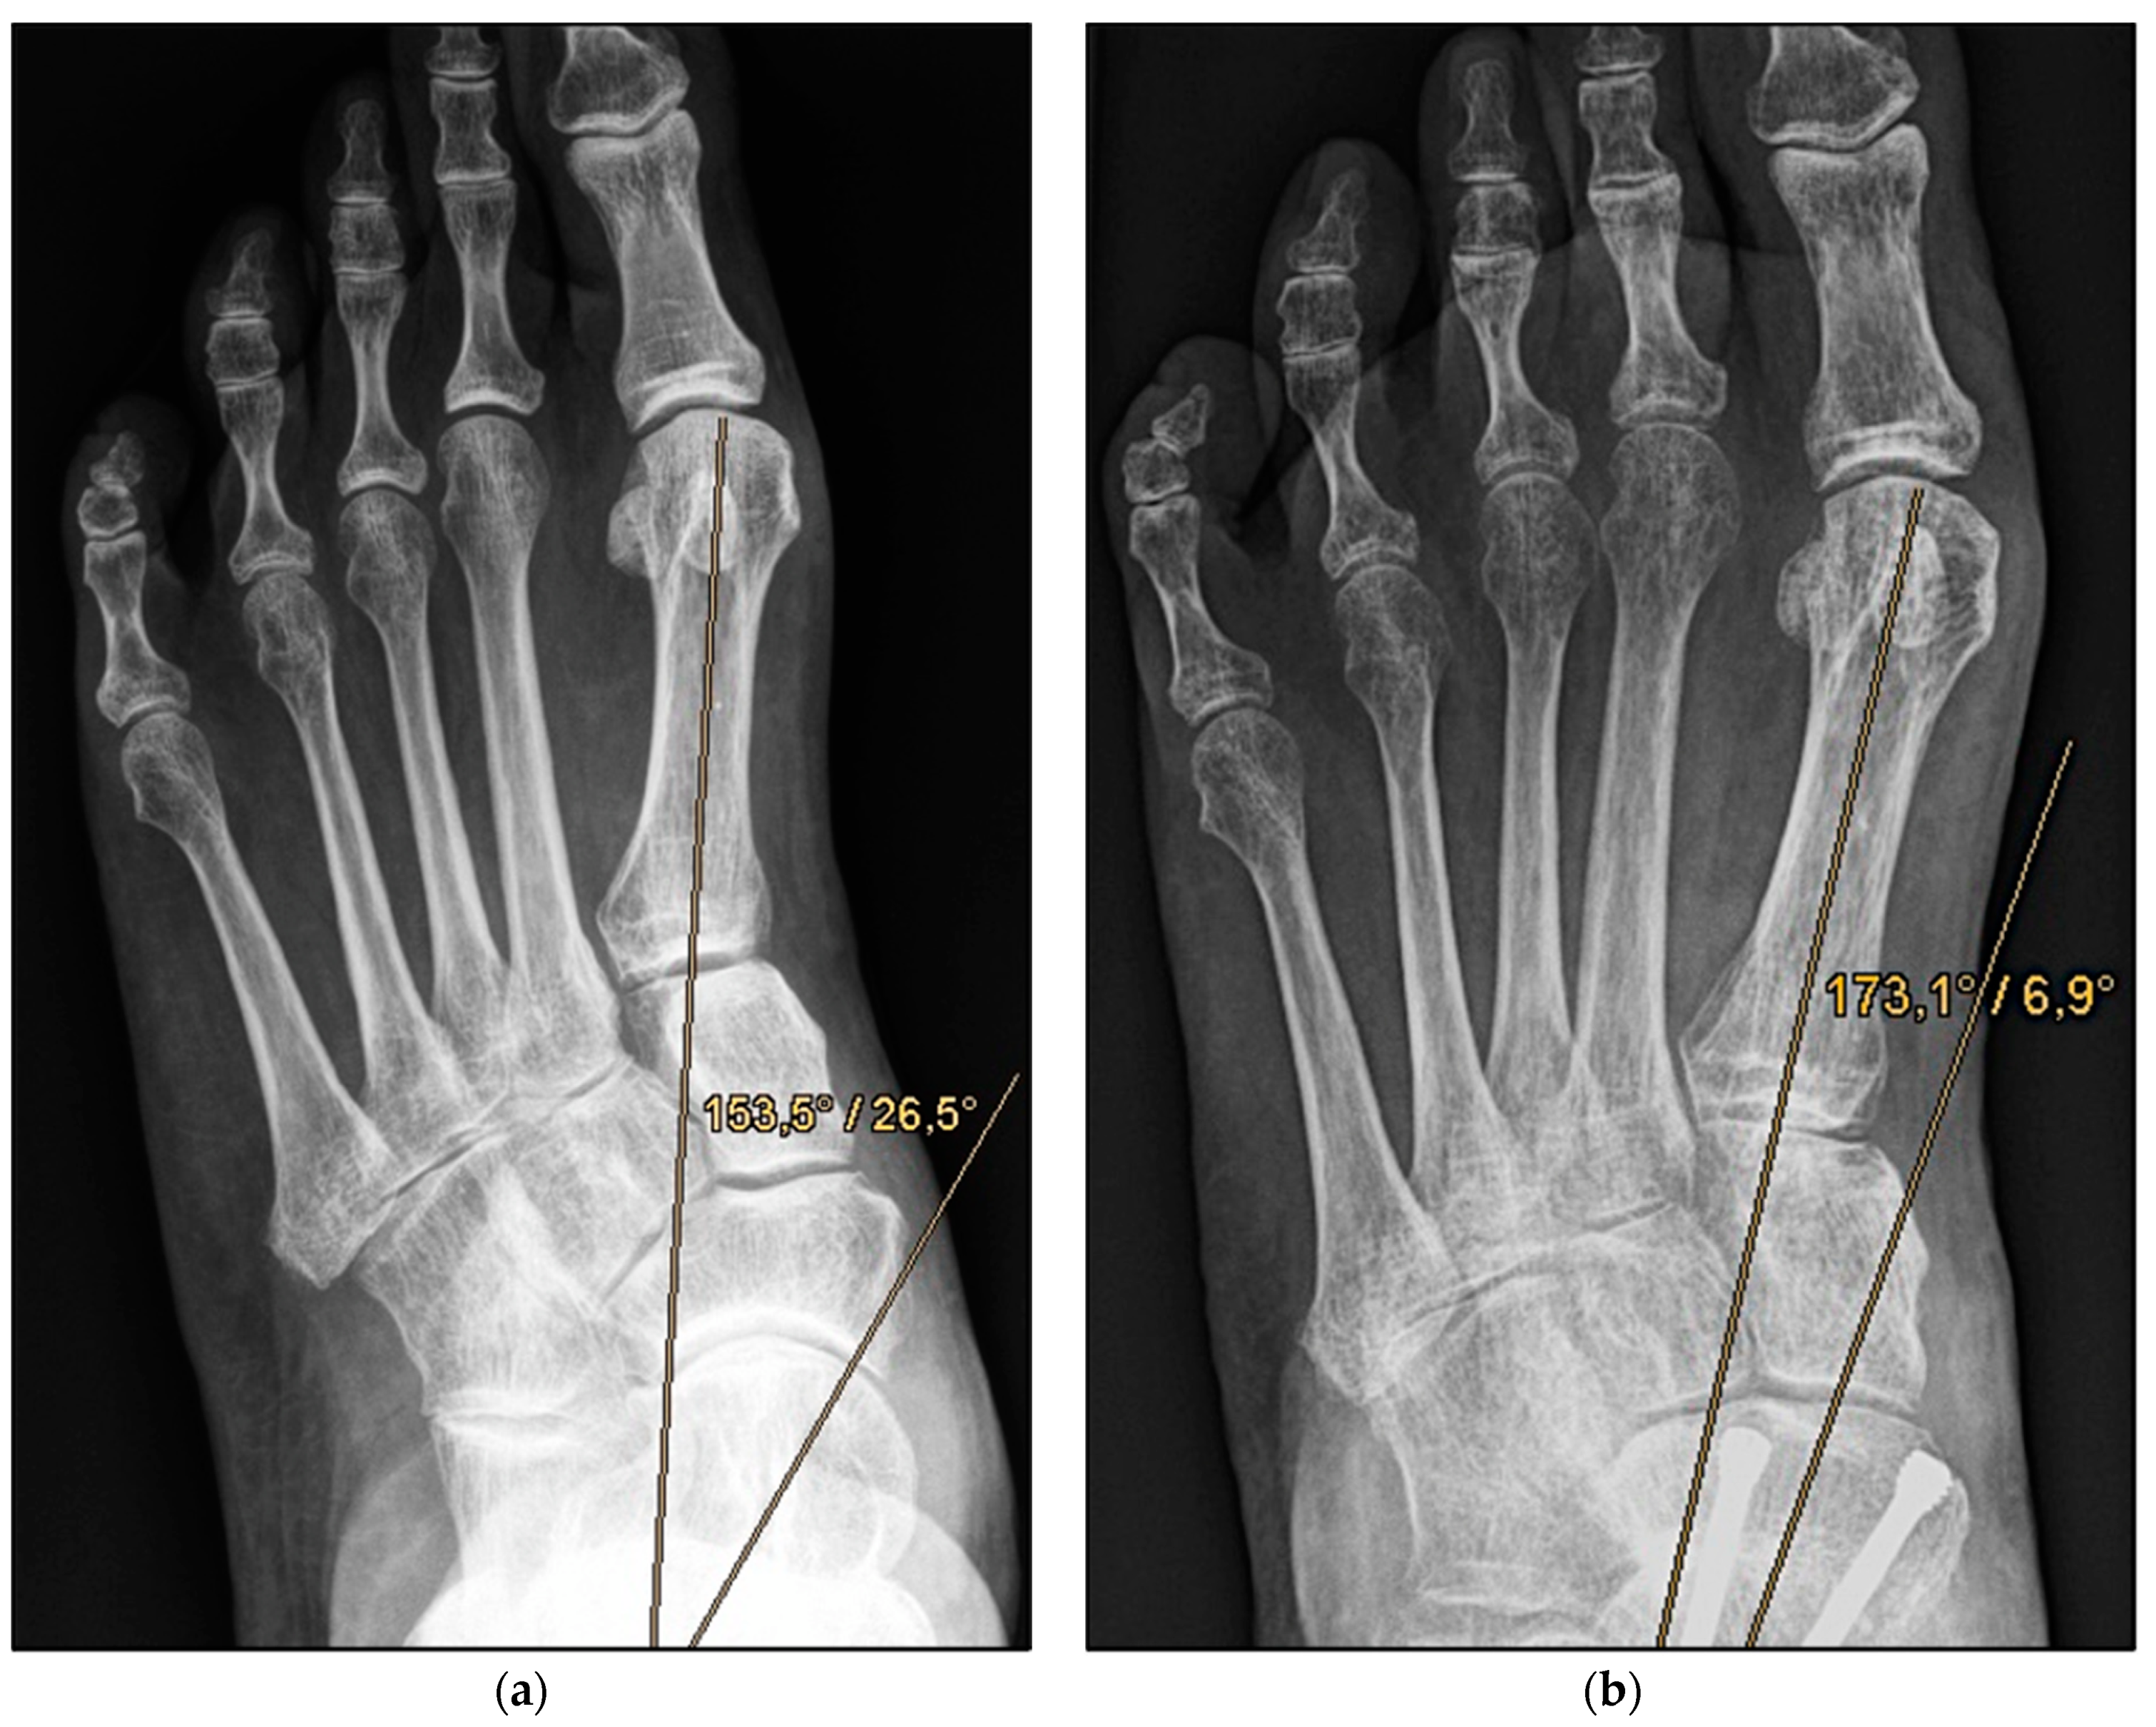

Figure 2.

Pre- and post-operative radiographic findings of combined talonavicular arthrodesis and calcaneal displacement osteotomy, left foot. (a) Anteroposterior view pre-operative, (b) anteroposterior view post-operative.

Medial calcaneal displacement osteotomy and talonavicular arthrodesis (Group A). In the first step, a V-shaped osteotomy was performed via an oblique approach to the lateral calcaneus with medial displacement of the back portion of the calcaneus. Osteotomy was performed using either an oscillating bone saw or bone chisel. Depending on the extent of the deformity, a medial displacement of approximately 8–10 mm was considered optimal. Fixation was achieved by means of two percutaneously inserted lag screws with diameters of 4.0–6.5 mm. The second step was talonavicular arthrodesis via a dorsal approach, usually with interposition of an iliac crest bone graft. Fixation was performed using two or three screws with diameters of 4 mm or a combination of screws and Nitinol compression implants (Figure 2a,b and Figure 3a,b).